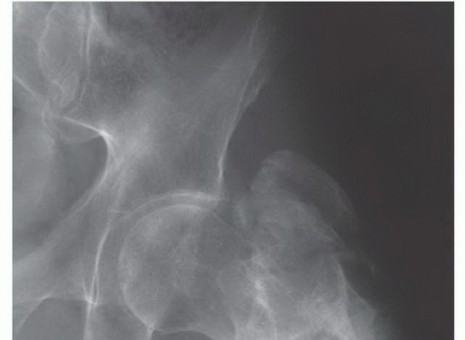

Before a single incision is made, the operating surgeon must possess a granular, three-dimensional understanding of the femoral anatomy and its surrounding neurovascular topography. The proximal femur is a complex biomechanical nexus, and its resection profoundly alters the force vectors acting across the hip joint. The intracapsular location of the femoral neck is of paramount oncologic significance. Tumors arising in or extending to the femoral neck can rapidly contaminate the hip joint via the synovial fluid. The ligamentum teres, an often-underappreciated structure, serves as a direct vascular and lymphatic conduit for transarticular skip metastases to the acetabular fovea. While true intra-articular tumor spill is relatively rare in the absence of a pathologic fracture, any preoperative clinical or radiographic suspicion of capsular invasion mandates an extra-articular resection of the hip joint—a significantly more morbid procedure involving the en bloc resection of the acetabulum.

The success or failure of a massive endoprosthetic reconstruction is largely determined before the patient ever enters the operating theater. Meticulous preoperative planning is the cornerstone of this procedure. The imaging suite is our primary intelligence-gathering tool. Full-length, weight-bearing orthogonal plain radiographs of the entire femur, hip, and knee are mandatory to assess overall alignment, leg length discrepancies, and the gross extent of bony destruction. However, the true roadmap for resection is provided by advanced cross-sectional imaging. High-resolution, multi-planar Magnetic Resonance Imaging (MRI) with and without gadolinium contrast is the gold standard for defining the intraosseous extent of the tumor (evaluating for skip metastases within the medullary canal) and delineating the extraosseous soft-tissue mass. The T1-weighted coronal and sagittal sequences are specifically utilized to determine the exact level of the bony osteotomy, aiming for a minimum of 2 to 3 cm of normal marrow beyond the MRI-defined tumor margin.